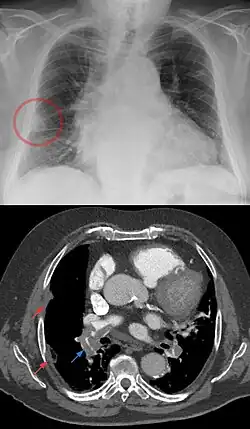

| A Hampton hump in a person with a right low lobe pulmonary embolism shown in CT in the lower image (blue arrow). | |

Hampton's hump, also called Hampton hump, is a radiologic sign which consists of a shallow wedge-shaped opacity in the periphery of the lung with its base against the pleural surface. It is named after Aubrey Otis Hampton, who first described it in 1940.[1] Hampton's hump along with Westermark sign may aid in the diagnosis of pulmonary embolism, although they are rare and their sensitivities and interoperator reliabilities are low. If the sign is present in an image, there is a high chance that the person has a pulmonary embolism, but when the sign is absent a pulmonary embolism is not ruled out.